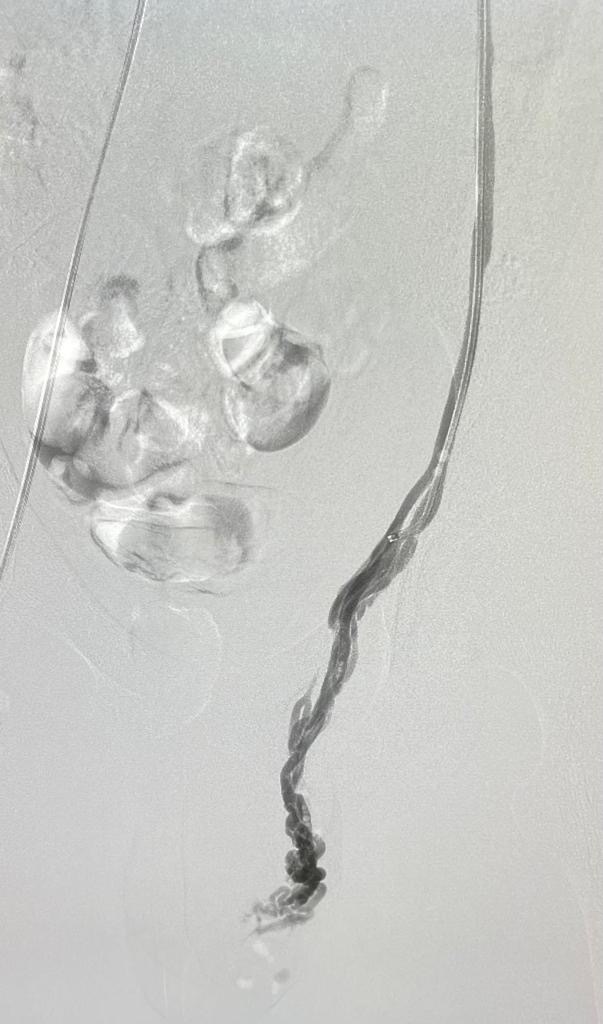

A varicocele is an enlargement of the veins within the loose bag of skin that holds your testicles (scrotum). It’s similar to a varicose vein you might see on your leg. Varicoceles are a common cause of low sperm production and decreased sperm quality, which can cause infertility.